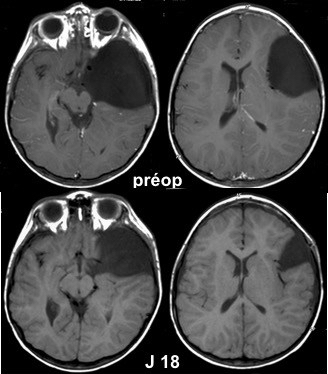

si au contraire le patient est symptomatique, s’il existe un effet de masse, une chirurgie est à proposer. idéalement, c’est une intervention endoscopique qui permettra au mieux de rétablir une circulation normale du LCS en déstabilisant le moins possible la situation ; le bénéfice de la chirurgie est à mettre en balance avec ses risques, en particulier la survenue d’une collection sous-durale.

cette chirurgie comporte un risque de complications, en particulier de collection sous-durale surtout chez le jeunes enfants, mais elle a l’avantage de la simplicité et d’un rapport bénéfice-risque favorable.

la seule solution est le drainage sous-dural, soit externe si le liquide des hémorragique, soit interne s’il est fluide. quand le liquide est eau-de-roche, il faut mettre en place une valve ; on a parfois en post-opératoire un syndrome d’hyper-drainage avec céphalées orthostatiques invalidantes.